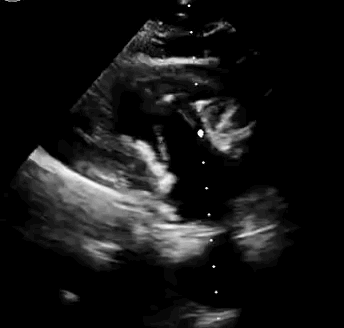

上海中山醫院葛均波院士、錢菊英院長、周達新教授、潘文志教授、潘翠珍教授、李偉教授共同完成此次臨床前研究。術后葛均波院士對Lux-Valve Plus的器械操作性能給予了高度評價,DSA和超聲影像也顯示出在本次研究中Lux-Valve Plus的安全性和有效性俱佳。

本次臨床前研究經右側頸靜脈置入LuX-Valve Plus輸送系統可調彎鞘管,在DSA及超聲引導下將人工三尖瓣瓣膜植入到原有三尖瓣位置,利用獨特的錨定技術將人工瓣膜支架可靠固定在預定的位置。